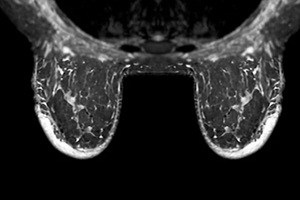

When you come in for breast cancer screening, your mammogram (or breast imaging study) generates more than just pictures. It produces a report with a Breast Imaging-Reporting and Data System (BI-RADS) score. It’s a classification system developed by the American College of Radiology to standardize how radiologists describe breast imaging findings and help determine future care.

- The BI-RADS system assigns a number from 0 to 6 as well as a breast density code to indicate how confident the radiologist is that a finding is benign or suspicious.